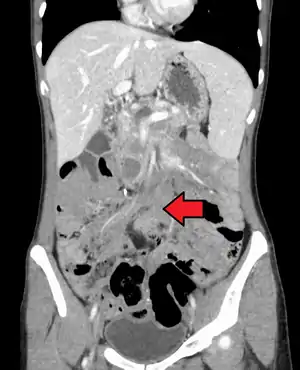

Desmoid tumor as seen on CT scan